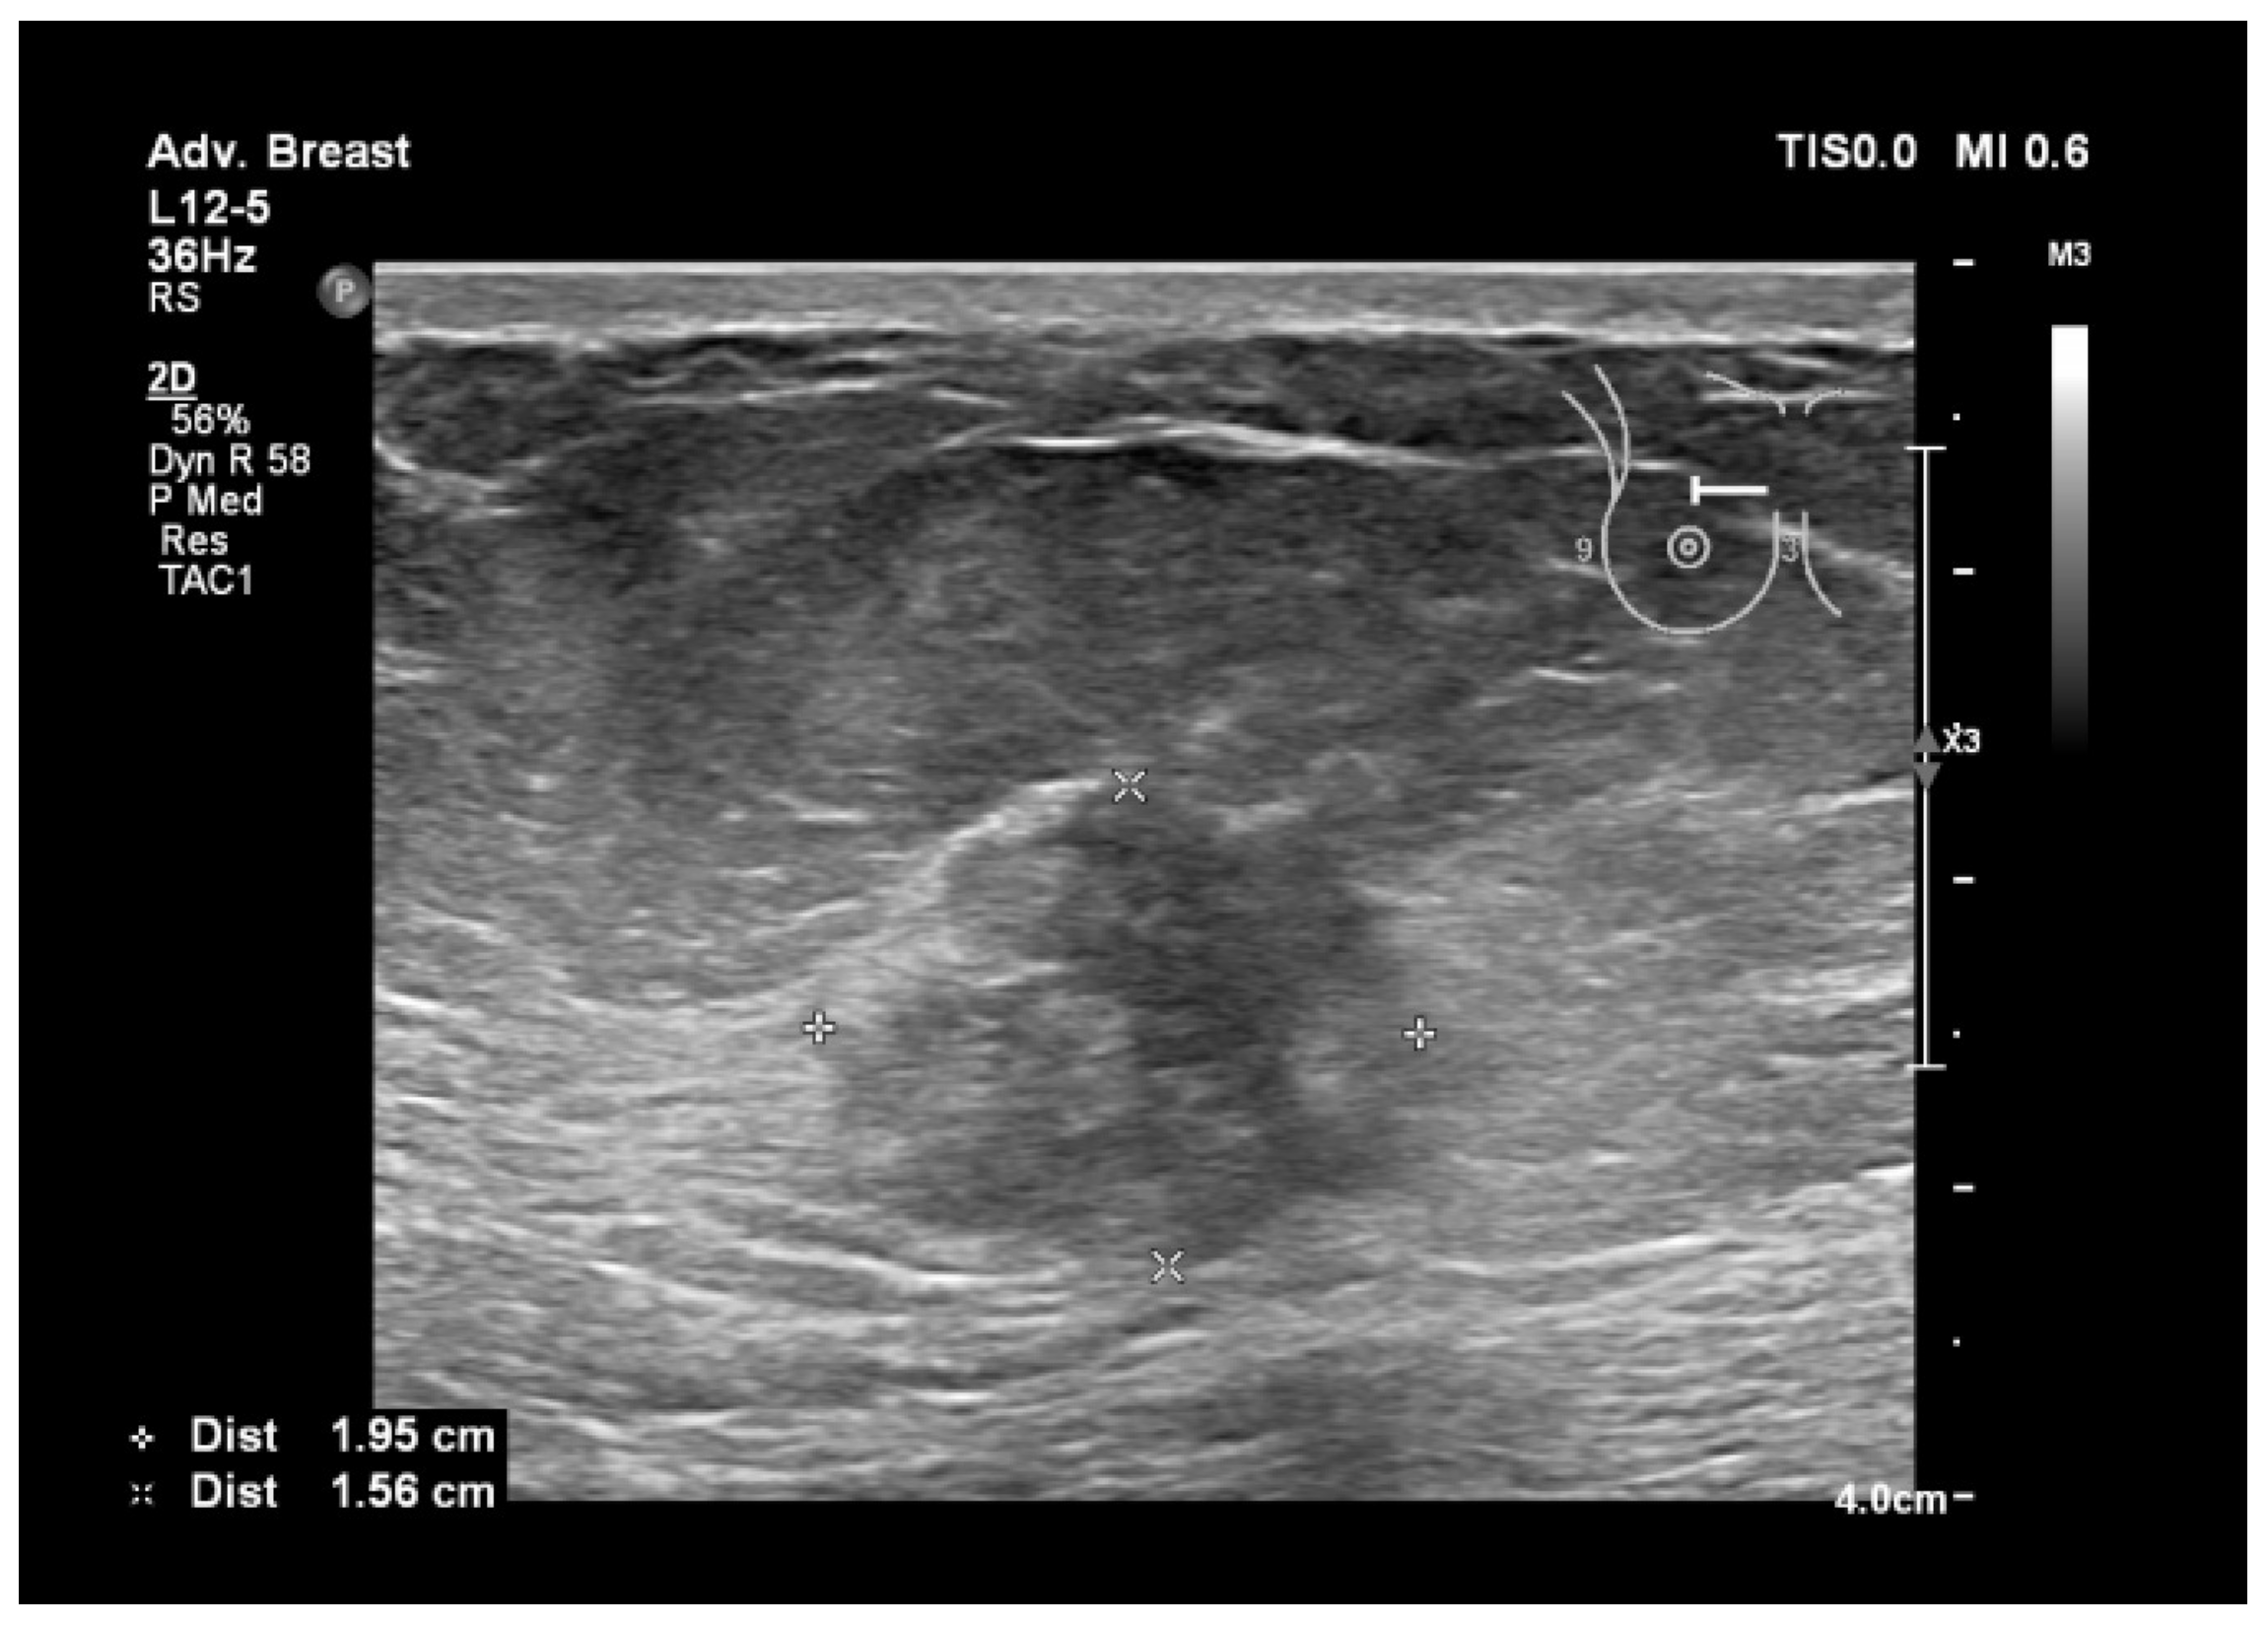

Figure 6.

Breast lesion detected using ultrasound, shows a heterogenous, hypoechogenic solid nodule, with spiculations and ill-defined margins.

Figure 5, Figure 6, Figure 7 and Figure 8, three suspicious lesions seen with ultrasound on the right breast, with the same malignant characteristics on the mammography (spiculations, ill-defined margins).